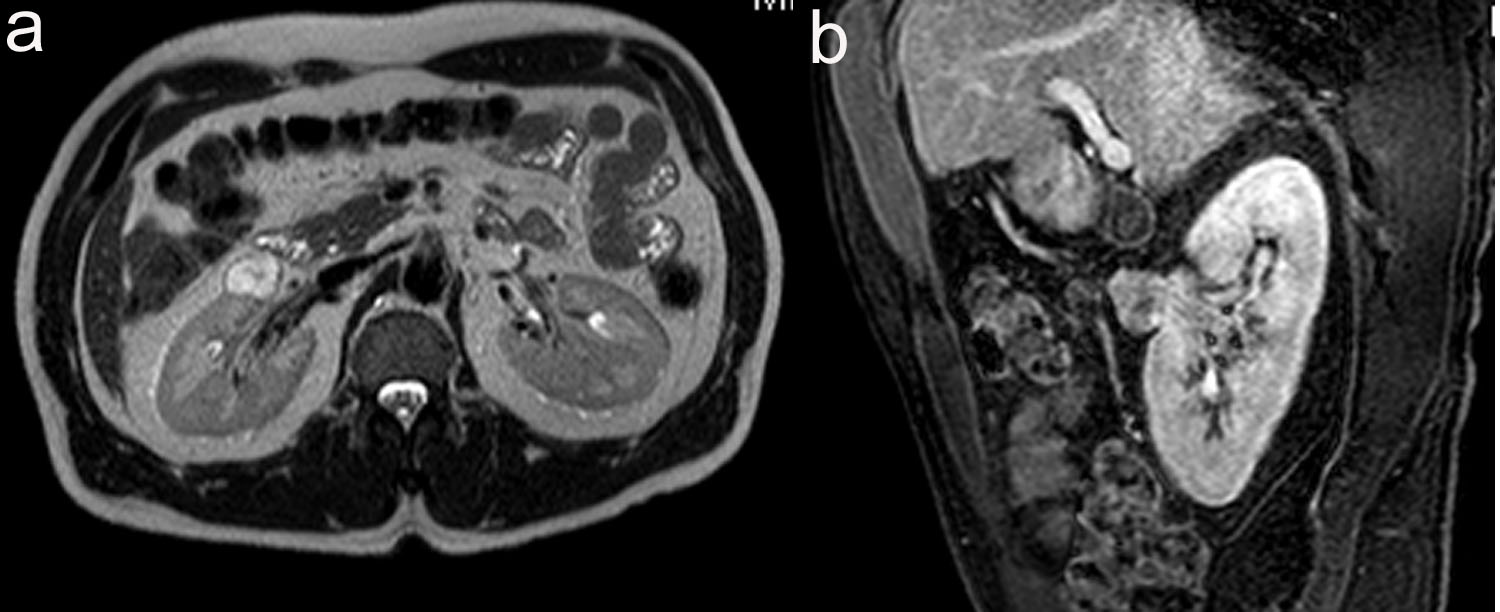

A 48-year-old male was referred to urology for an incidentally found right complex renal mass. The patient denied any urinary symptoms as well as gross hematuria. Urinalysis was also negative for microscopic hematuria. He has a past medical history of chronic Hepatitis B and Raynaud’s disease. The patient initially had an MRI study which revealed a 2.4 cm multi-septated cystic mass in the right kidney. The decision was made to place the patient on surveillance for this lesion. At 1-year follow-up, repeat MRI study revealed 2.4 cm T2 hyperintense, enhancing soft tissue renal mass concerning for renal cell carcinoma (Fig. 1). Given this change in appearance, patient underwent an uneventful right laparoscopic partial nephrectomy.

![]() Click for large image | Figure 1. (a) 2.1 cm x 2.3 cm x 2.4 cm, T2 hyperintense, enhancing soft tissue renal mass anterior to interpole of right kidney. (b) Sagittal view of T1 weighted thrive sequence. |